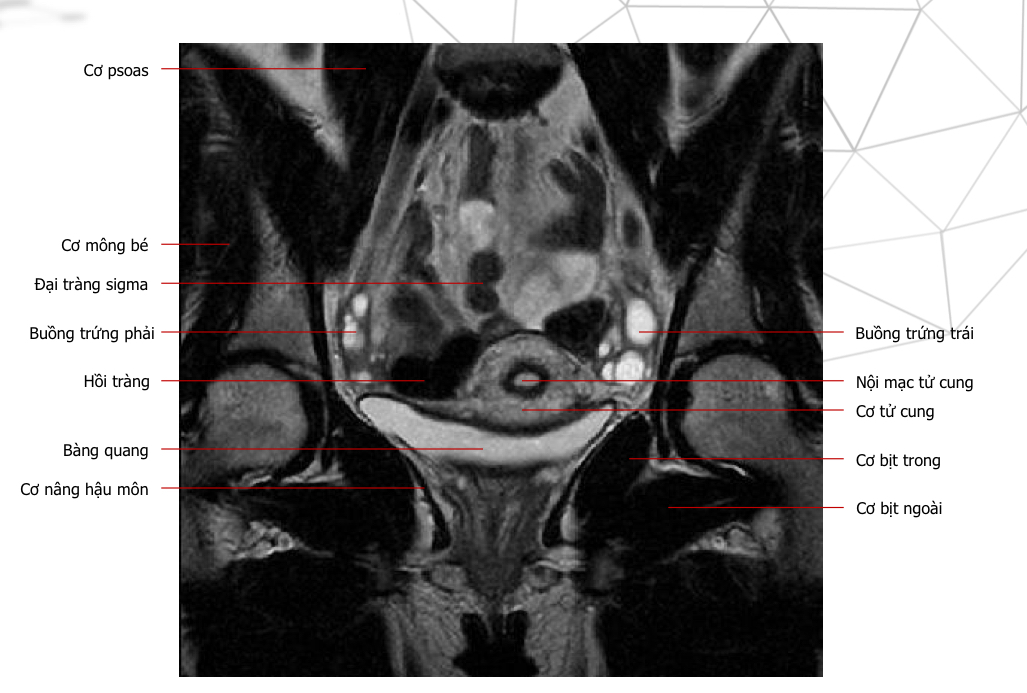

Mốc gp, chuỗi xung, thì

Thì nghỉ, T2w ax

chuỗi xung, thì, mốc gp

T2 cor, thì nghỉ